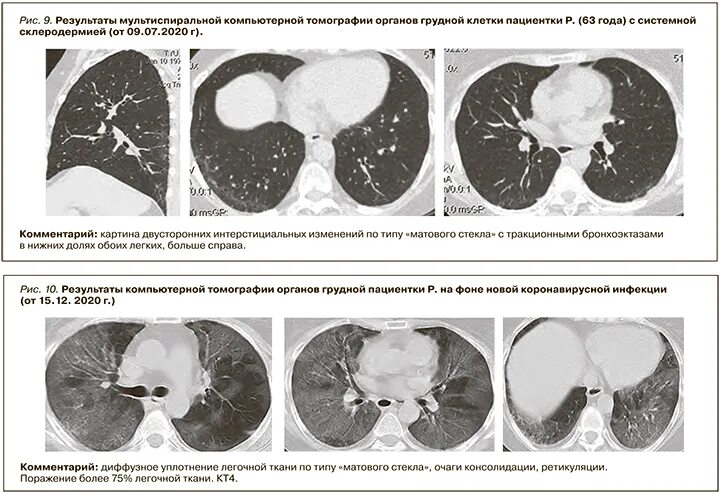

Дексаметазон при ревматоидном артрите